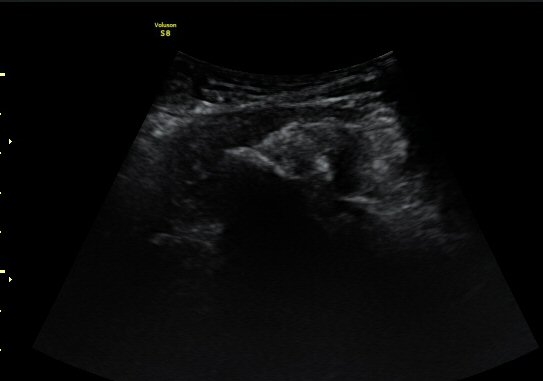

ÃÊÀ½ÆÄ °Ë»ç

¾ûµ¢ÀÌ °üÀý Á¾´Ü¸é°Ë»ç¿¡¼­ ƯÀÌ ¼Ò°ßÀ» º¸ÀÌÁö ¾ÊÀ½(»çÁø 1).

ŽÃËÀÚ¸¦ ¾ûµ¢ÀÌ °üÀý ¿ÜÃø Á¾´Ü¸é°Ë»ç ½Ã ÀüÇÏÀ屨(AIIS)¿¡¼­ ¼®È¸È­¼º À½¿µÀÌ °üÂûµÊ(»çÁø 2, 3).

¼±»óŽÃÊÀÚ¸¦ ÀÌ¿ëÇÑ °Ë»ç¿¡¼­ ÀüÇÏÀ屨ÀÇ ´ëÅðÁ÷±Ù ±â½ÃºÎ¿¡ ¼®È¸È­ À½¿µÀÌ ¶Ñ·ÈÈ÷

°üÂûµÊ(»çÁø 4, 5).